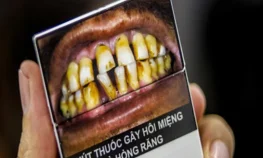

Hút Thuốc Tăng Nguy Cơ Mắc Bệnh Nha Chu Gấp 6 Lần

08/05/2025

Không chỉ là nguyên nhân gây ra các bệnh lý tim mạch, hô hấp và ung thư, hút thuốc còn là một trong những yếu tố nguy cơ hàng đầu dẫn đến bệnh nha chu - một trong… -